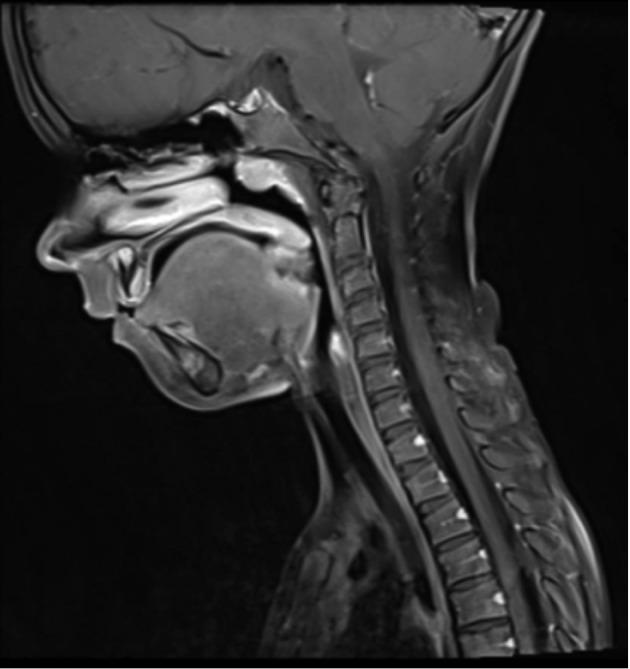

Surgical tracheostomy is a life-saving procedure performed for emergent or expectant airway compromise. Morbidity in the pediatric population is higher than in adults due to smaller operating field, immaturity of tissues, anatomic specificities of the child's neck, or the presence of craniofacial dysmorphism. The procedure varies among surgeons regarding the position of the skin incision (vertical or horizontal), resection of the subcutaneous adipose tissue and isthmus of the thyroid gland, use of tracheal flaps, and use of maturation or stay sutures. Both early and late complications can be life-threatening, and include accidental decannulation, stomal plugging, bleeding, and difficult ventilating. Consistent tracheostomal care is crucial in avoiding complications. Primary caregivers must be included and educated about proper stomal care. Decannulation failures are common. Prerequisites for safe decannulation include non-dependence on mechanical ventilation and no recent aspiration events, positive endoscopic airway assessment, and successful daytime capping. The role of polysomnography in decannulation protocols is debated. Although seldom performed, tracheostomy is the procedure of choice in a selected group of pediatric patients. The risks and benefits of the procedure must be weighed for each patient. The education of medical personnel and caregivers is key to reducing serious complications.